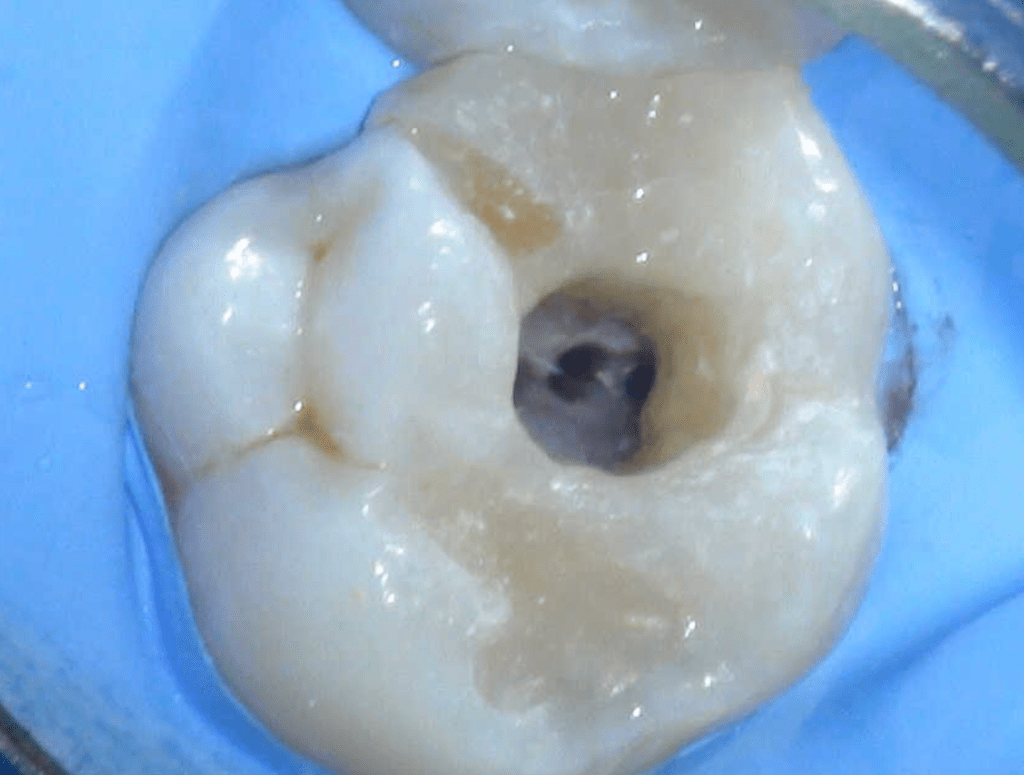

Reco pre-endo, molar inferior